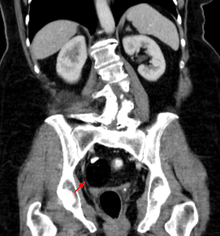

Beyond the newborn period, symptoms of a teratoma depend on its location and organ of origin. Ovarian teratomas often present with abdominal or pelvic pain, caused by torsion of the ovary or irritation of its ligaments. A recently discovered condition where ovarian teratomas cause encephalitis associated with antibodies against the N-methyl-D-aspartate receptor (NMDAR) - often simply referred to as "Anti-NMDA receptor encephalitis", was identified as a serious complication. Patients develop a multistage illness that progresses from psychosis, memory deficits, seizures, and language disintegration into a state of unresponsiveness with catatonic features often associated with abnormal movements, and autonomic and breathing instability.[18] Testicular teratomas present as a palpable mass in the testis; mediastinal teratomas often cause compression of the lungs or the airways and may present with chest pain and/or respiratory symptoms.